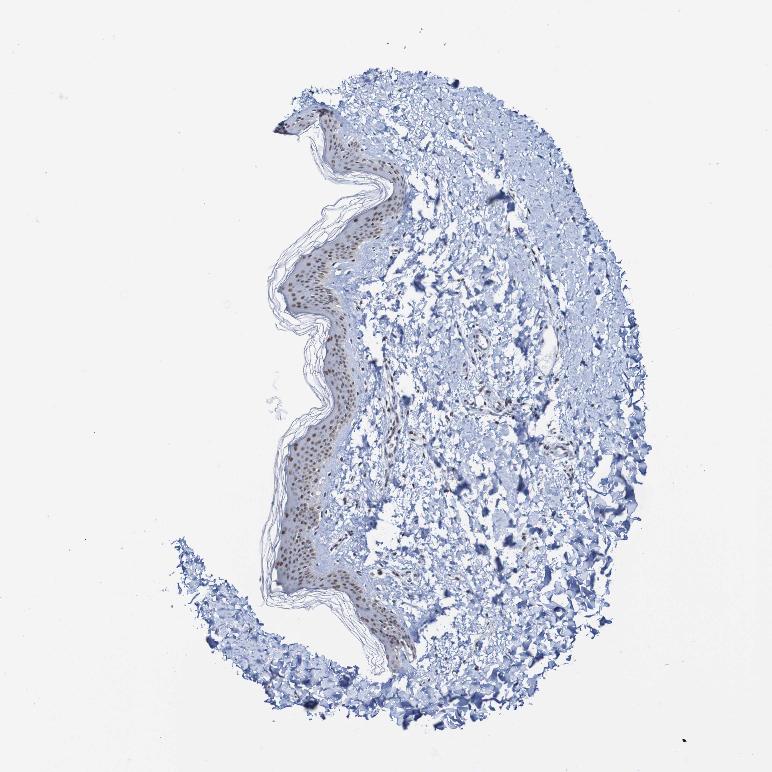

SKIN 1 - Antibody stainingi

Antibody staining in the annotated cell types in the current human tissue is reported as not detected, low, medium, or high, based on conventional immunohistochemistry profiling in selected tissues. This score is based on the combination of the staining intensity and fraction of stained cells.

Each image is clickable and will lead to virtual microscopy that enables deeper exploration of all samples and also displays staining intensity scores, fraction scores and subcellular localization as well as patient and tissue information for each sample.

Antibody HPA006302Antibody HPA011361Antibody CAB012275

Langerhans HighMediumMedium

Fibroblasts MediumMediumMedium

Keratinocytes HighMediumMedium

Melanocytes HighMediumMedium

SKIN 2 - Antibody stainingi

Epidermal cells HighMediumMedium